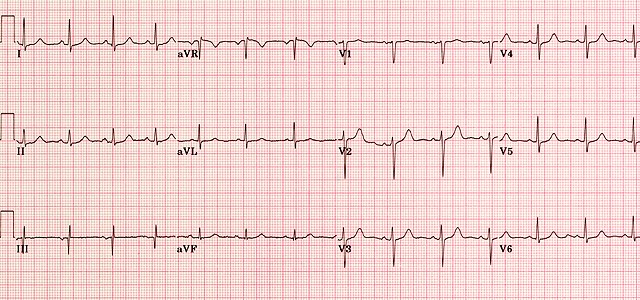

Relevant Test Results Prior to Catheterization

Resting ECG was normal. Normal resting LV function without RWMA.Renal function was normal.